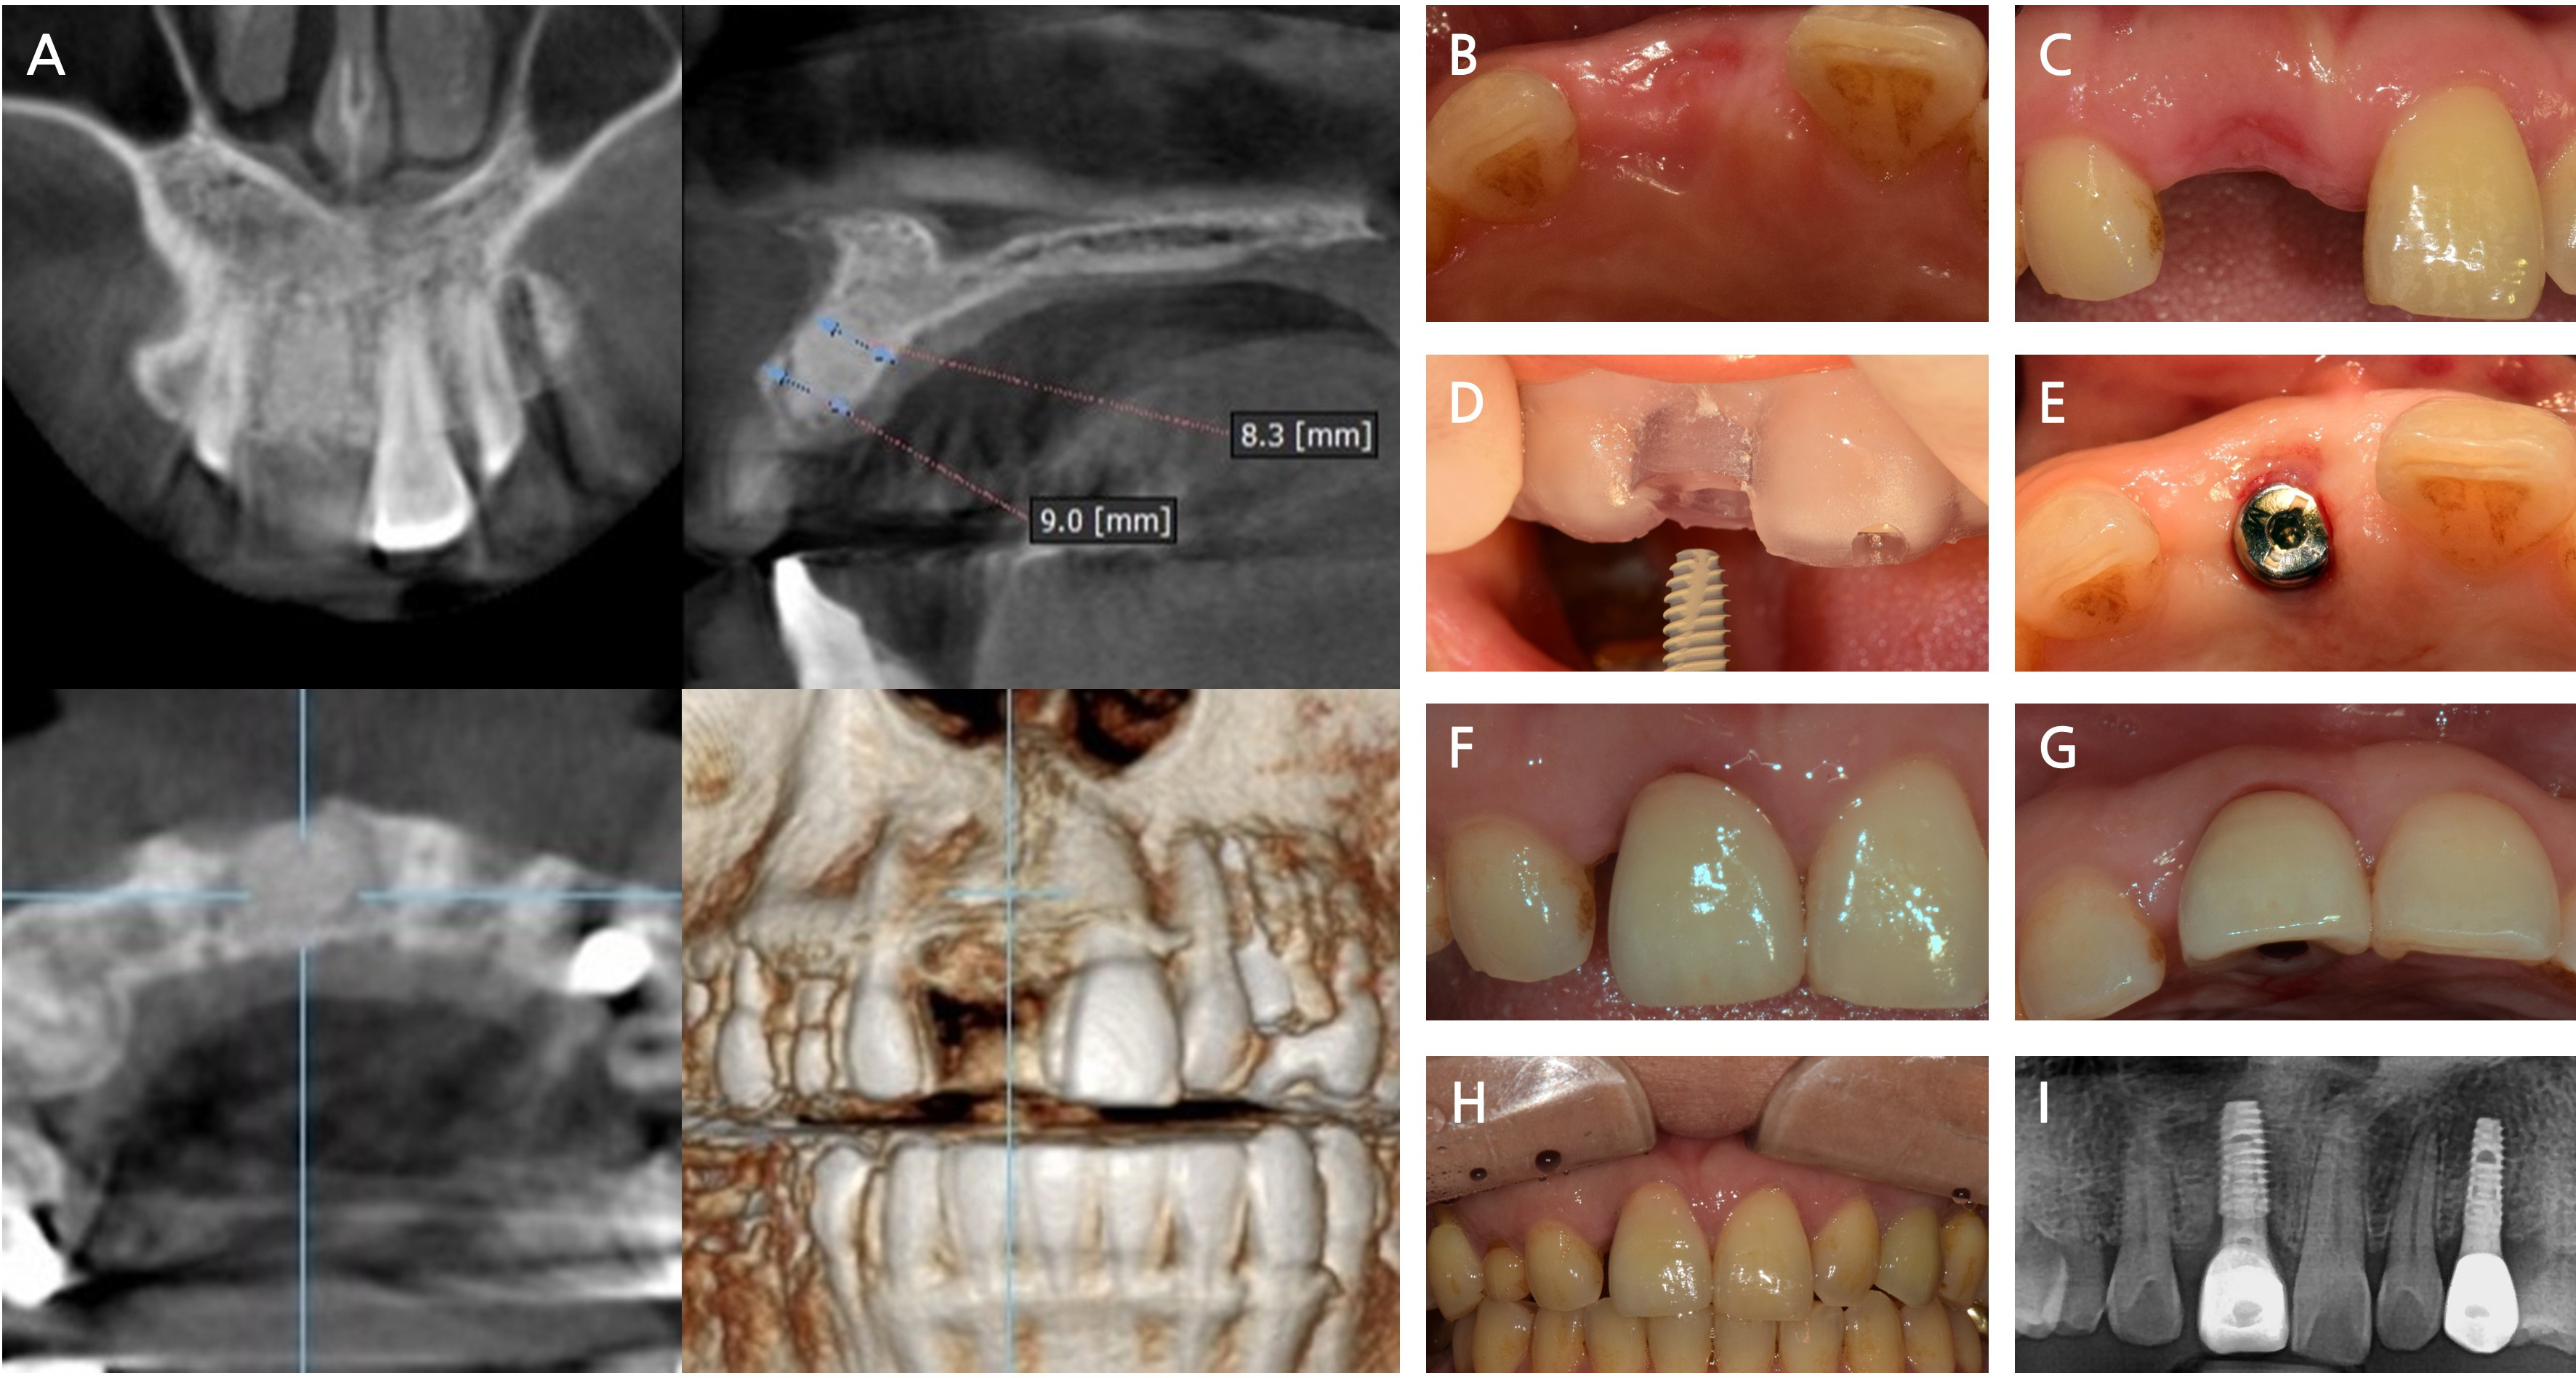

Following 2 months of uneventful healing (Fig. 5A to 5C), an internal-type dental implant (Superline®; Dentium, Suwon, Korea) was placed using a computer-guided surgical guide (Fig. 5D and 5E). The final prosthetic restoration was delivered 6.5 months after the initial ARP procedure using intrasocket granulation tissue repositioning (Fig. 5F and 5G). Radiographic and clinical evaluations performed 18 months after surgery confirmed a stable peri-implant marginal bone levels without resorption, along with healthy surrounding soft tissues, indicating periodontal stability (Fig. 5H and 5I).

Fig. 5

Surgical procedure of implant placement and follow-up outcomes after alveolar ridge preservation (ARP) using intrasocket granulation tissue repositioning. (A) A cone-beam computed tomography image 2 months after ARP showing adequate bone volume for implant placement, (B, C) Preoperative clinical images demonstrating stable soft tissue contour and adequate ridge dimensions, (D) Implant placement using computer-guided surgery based on a customized surgical stent, (E) Healing abutment installed following implant insertion, (F, G) Final prosthesis delivered 6.5 months after ARP, showing satisfactory esthetic integration with the surrounding tissue, (H, I) Clinical and radiographic evaluation 18 months postoperatively, revealing stable marginal bone level and healthy peri-implant soft tissue.